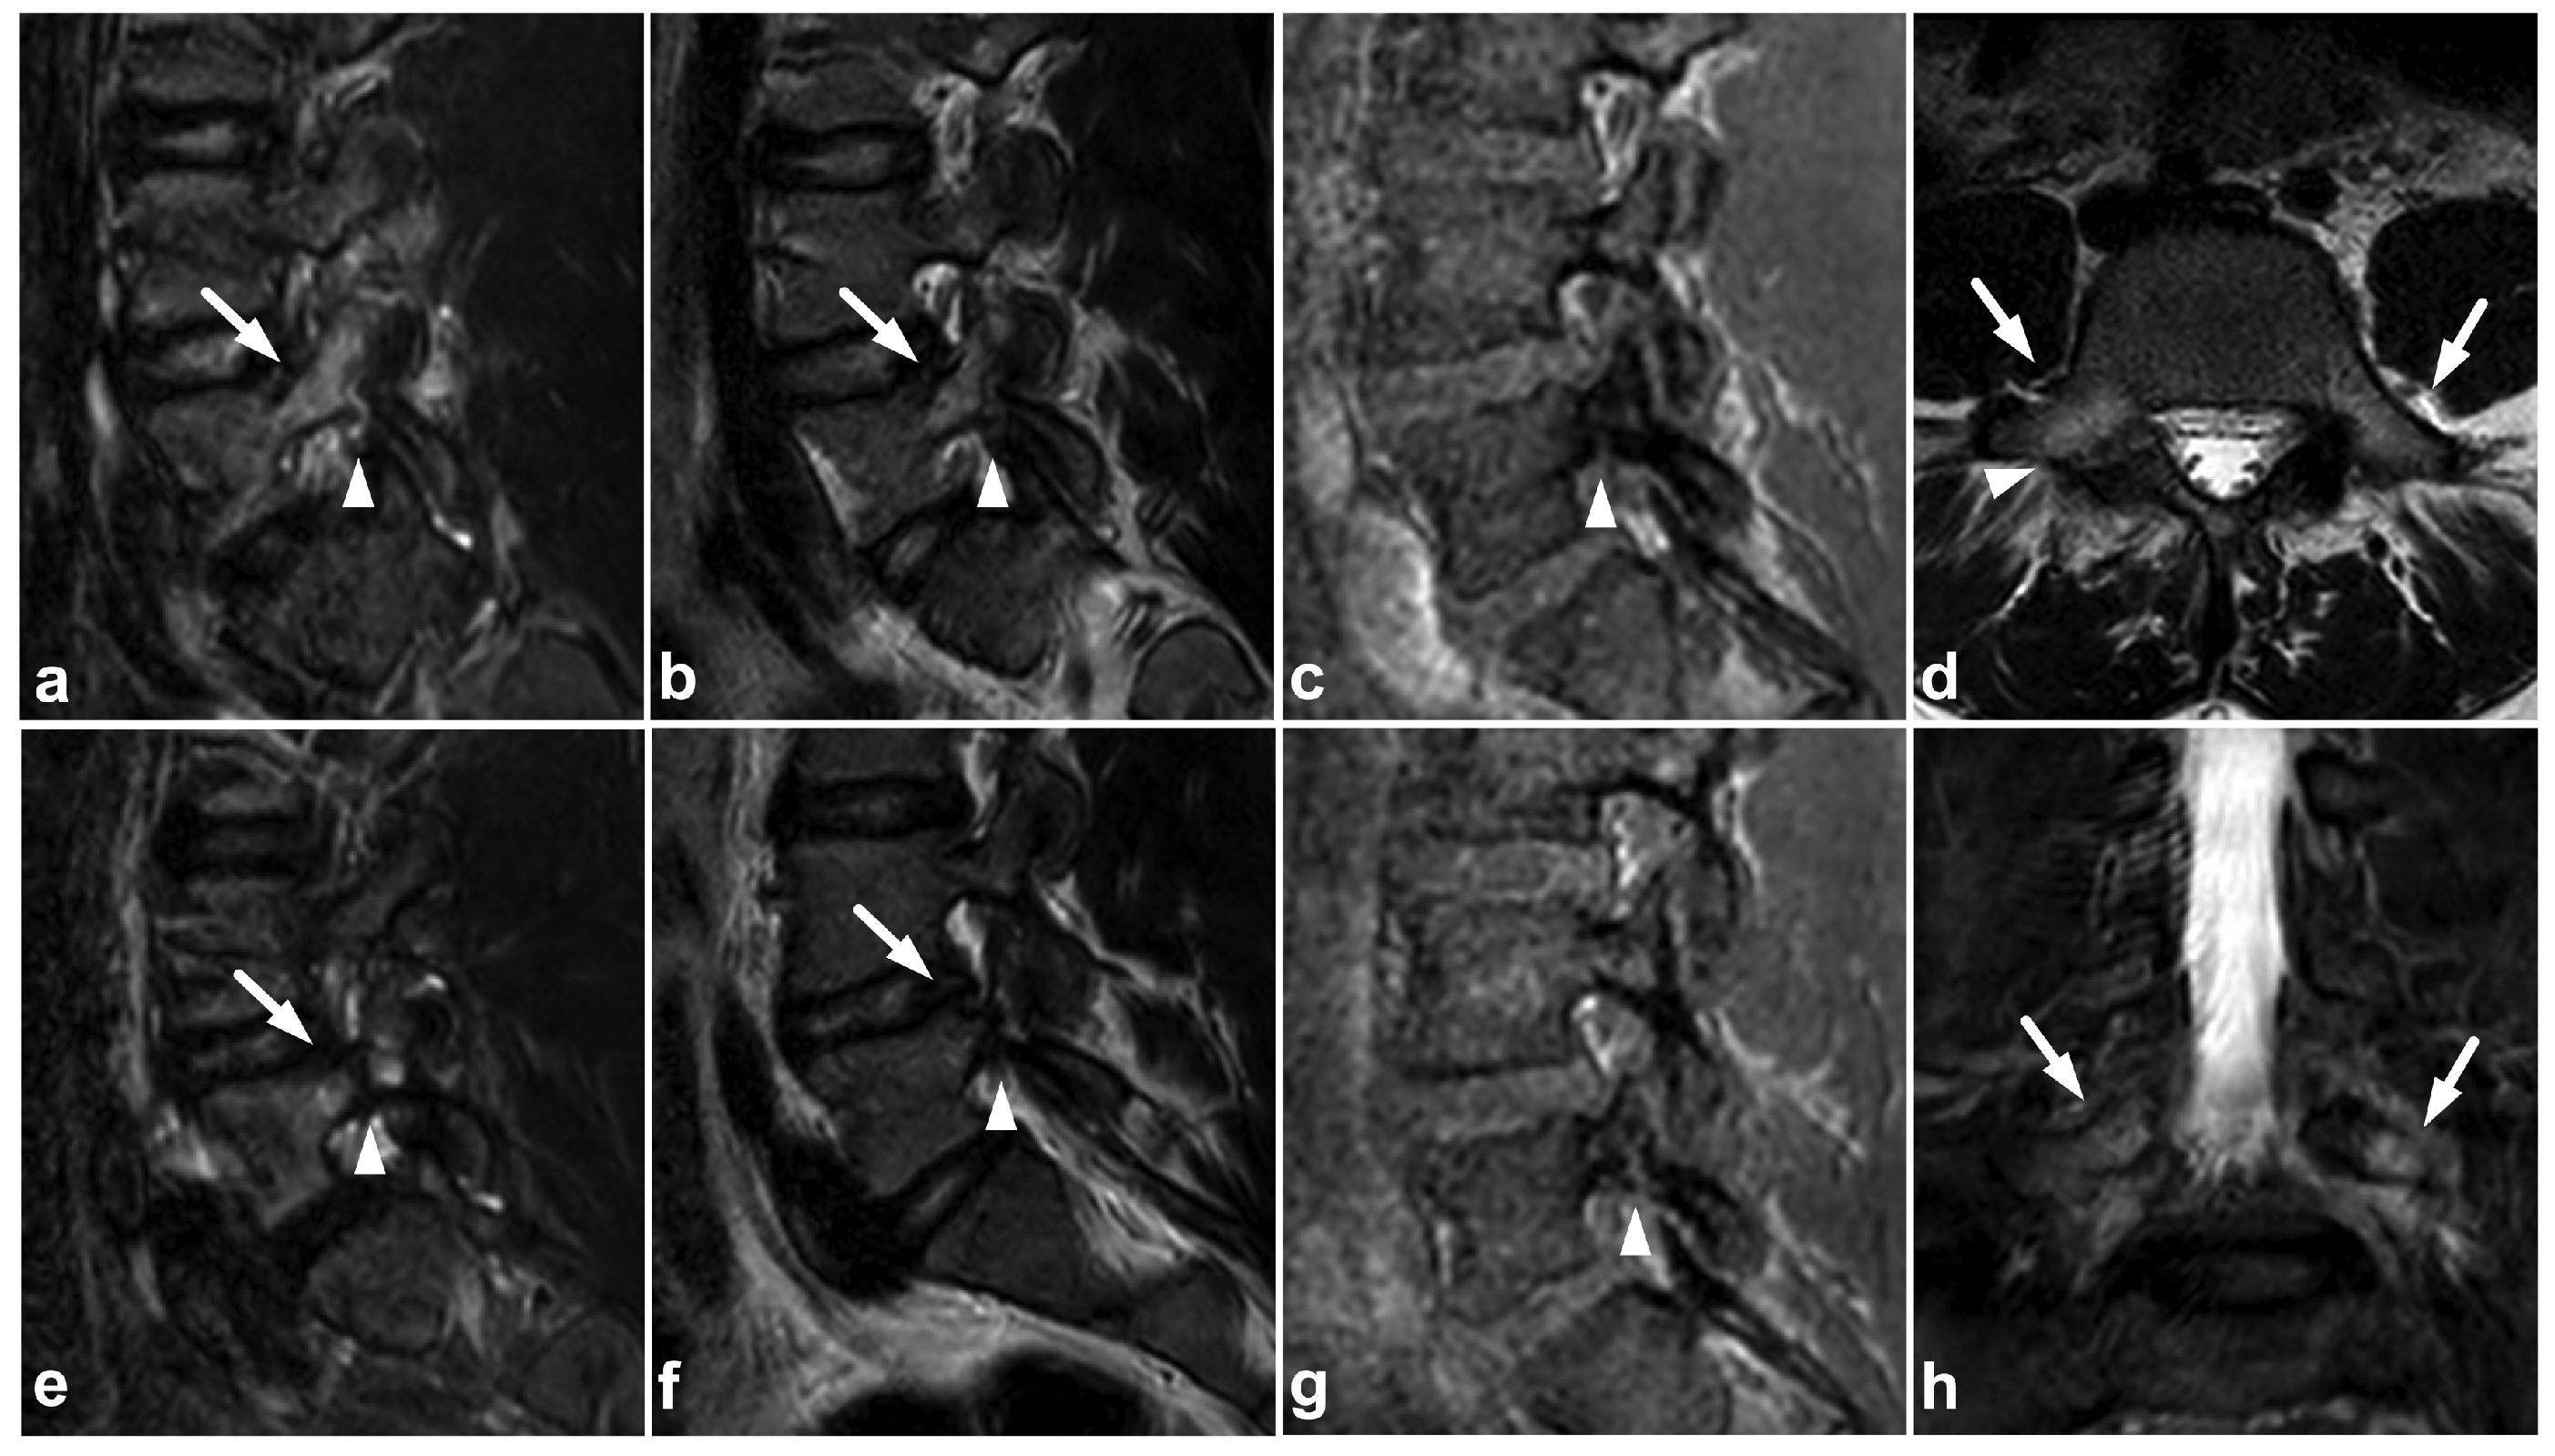

Figure 19.

(a) Sagittal right-sided off-midline STIR. (b) Sagittal right-sided off-midline T2-weighted. (c) Sagittal right-sided off-midline black bone sequence. (d) Axial T2-weighted. (e) Sagittal left-sided off-midline STIR. (f) Sagittal left-sided off-midline T2-weighted. (g) Sagittal left-sided off-midline black bone sequence. (h) Coronal STIR. A 12-year-old female with acute lower back pain when playing with friends. MRI demonstrates bilateral bone marrow edema centered in pars interarticularis (arrows). Fracture lines are also seen bilaterally in the pars (arrowheads). No spondylolisthesis is present.

7.3. Juvenile Spondylolysis

Juvenile lumbar spondylolysis ensues from repetitive stress, but the onset of symptoms can be sudden, and the chronic pain may be exaggerated by acute trauma. The clinical presentation and the typical location of the findings centered in the pars interarticularis help to distinguish a stress injury from an acute traumatic fracture. The spondylolysis and surrounding bone marrow edema can probably be assessed with MRI [80], but the evidence of MRI’s sensitivity is not fully concurrent [81]. However, it seems that MRI’s performance can be improved with high-resolution T1-weighted sequences optimized for bony structures [82] or with a novel ultrashort time-to-echo technique [83]. An example of a lumbar spondylolysis is presented in Figure 19. Targeted small-FOV CT may be used in estimating the age, grade, and bony union rate of the spondylolysis in treatment planning and follow-up [82,83,84,85,86].